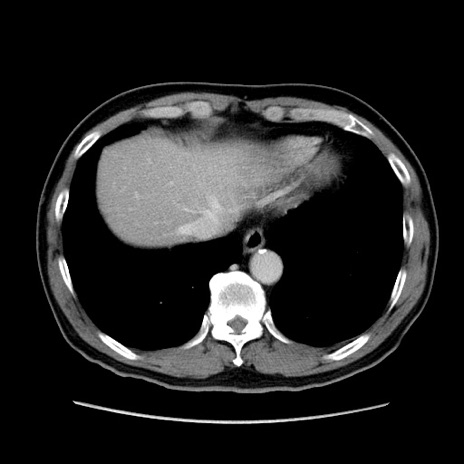

症例34(横断像)

【症例】60歳代 男性

【主訴】右鼠径部膨隆

【現病歴】1年程前より右鼠径部膨隆あり。自己にて還納可能だったため放置していた。3時間前より右鼠径部の脱出を認め、還納困難となり受診。

【身体所見】右鼠径部に小児頭大の膨隆あり。弾性硬であり、用手還納は困難。左鼠径部にも膨隆を認める。脱出はなし。